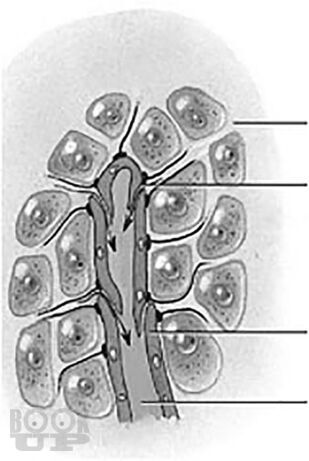

В учебном пособии в краткой и доступной форме излагаются современные сведения о строении лимфатической и иммунной систем. Латинская и русская анатомическая терминологии приведены в соответствии с Международной анатомической номенклатурой, принятой Федеративным комитетом по анатомической терминологии (FCAT, 1998). Учебное пособие включает опорные термины, необходимые при изучении соответствующих анатомических образований, а также тестовые задания и ситуационные задачи, что поможет обучающимся в освоении большого фактического материала при изучении путей транспорта лимфы, топографии регионарных групп лимфатических узлов и строения органов иммунной системы. Представлены современные методы визуализации лимфатической системы. Издание снабжено большим количеством схем и рисунков, взятых из открытых источников, что облегчает понимание организации лимфатической и иммунной систем.